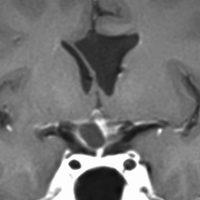

鞍隔膜上 supradiaphragmic type

この子の症状は頭痛だけ。両親はなぜ気づかなかったのかと疑問を持ちますが,巨大になるまで症状が出ないこともあるのです。左のCTで腫瘍の周囲にバラバラと白い点状の石灰化があるので診断できます。左の視床下部から発生したクラニオでした。開頭手術しますが超高難易度です,怖いです (┯_┯) 複数回開頭手術になりましたが結果的に全摘出できています (by Dr 山本哲哉)。